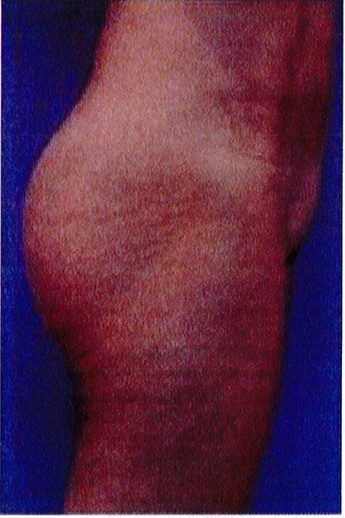

Hình. 18.. (A) Hình anh trước và (B) và sau phẫu thuật làm đầy mông của bệnh nhân được đặt khối implant dưới cân thể tích 225 mL, hai bên.

Bệnh nhân 31 tuổi tiền sử khỏe mạnh, có chỉ định nâng mông bằng implant do thiếu hụt thể tích. Hai khối anatomic implant 225 mL polyurethane dạng gel được đặt ở vị trí dưới cân. Sau phẫu thuật không ghi nhận biến chứng trong suốt quá trình hồi phục, vết mổ liền tốt (Hình 18).